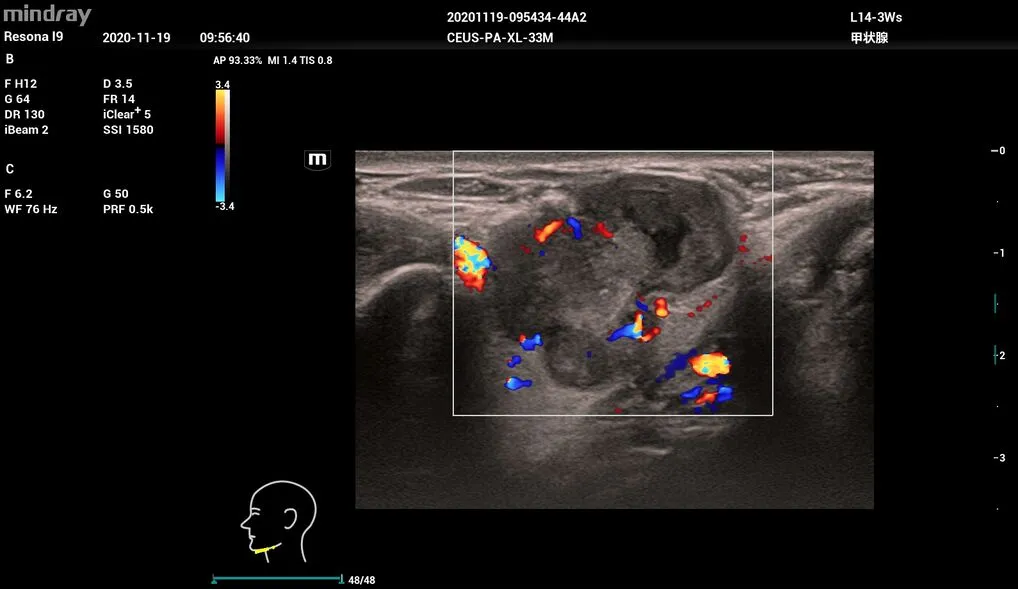

Оценка состояния узлов щитовидной железы Smart Thyroid

Метод интеллектуальной и стандартизированной оценки узлов щитовидной железы, реализованный в Resona I9 от Mindray, это автоматический анализ отсканированных в нескольких плоскостях областей по шкале TI-RADS, что даёт возможность более точной классификации узлов. Удобство работы обеспечивает оптимизация процесса.

- L14-3Ws – линейный датчик для исследования сосудов, органов брюшной и грудной полости, педиатрии.

Опухоль, L14-3Ws